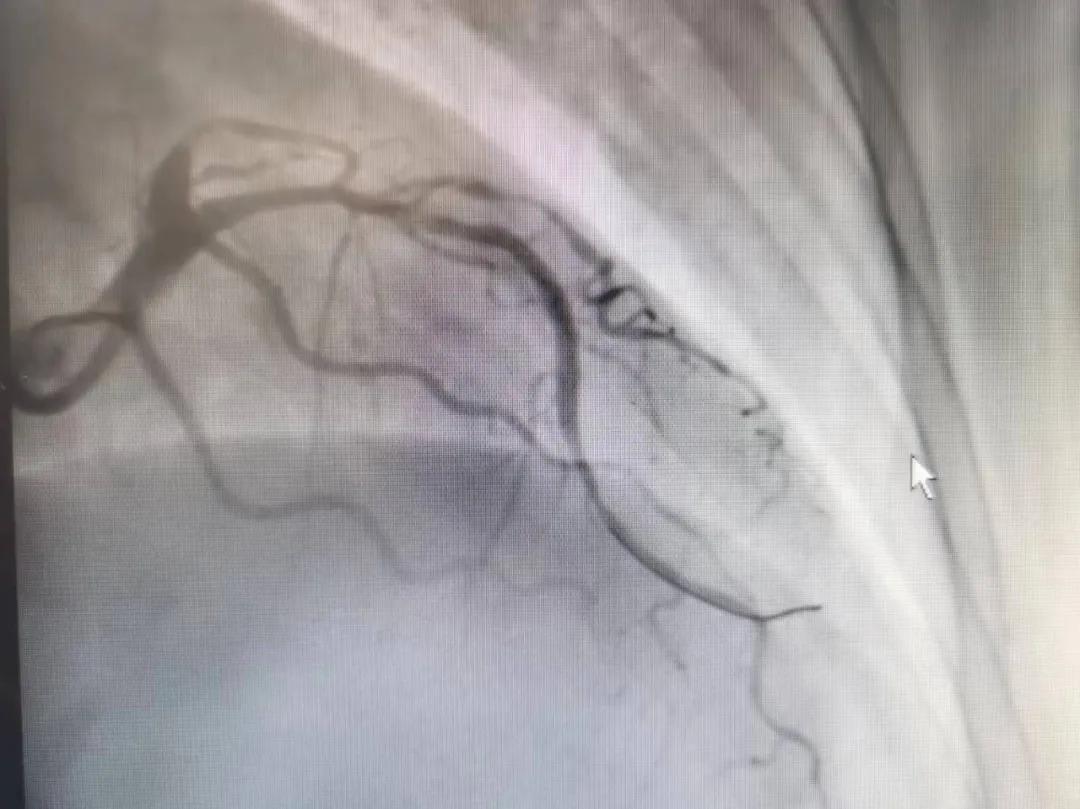

病人是位六十多歲的女性患者,有長(zhǎng)期高血壓病史,1個(gè)月前開(kāi)始出現(xiàn)胸悶胸痛,口服藥物治療效果不佳,經(jīng)朋友介紹,來(lái)到市二院心血管內(nèi)科。入院后完善冠狀動(dòng)脈造影提示:前降支全程彌漫性狹窄伴鈣化,最重95%,回旋支狹窄約85%,右冠脈全程狹窄伴鈣化,最重60%。血管內(nèi)超聲顯示右冠脈開(kāi)口面積3.36mm²,可見(jiàn)環(huán)形鈣化,考慮患者病變程度重、鈣化明顯,常規(guī)器械無(wú)法實(shí)現(xiàn)病變的良好預(yù)處理,且有很高的冠脈穿孔、血管夾層的風(fēng)險(xiǎn)。

術(shù)前

王瑾院長(zhǎng)和李慧新主任帶領(lǐng)介入團(tuán)隊(duì)充分評(píng)估,決定行前降支冠狀動(dòng)脈鈣化病變旋磨術(shù),術(shù)中應(yīng)用1.5mm旋磨頭,以15萬(wàn)-17萬(wàn)轉(zhuǎn)/分速度共對(duì)病變旋磨3次,累計(jì)旋磨時(shí)間60秒,后復(fù)查造影示鈣化明顯減輕,為后續(xù)操作創(chuàng)造了良好條件,隨后應(yīng)用預(yù)擴(kuò)張球囊、切割球囊再次處理病變,并順利植入支架1枚,復(fù)查造影顯示支架膨脹及貼壁良好,無(wú)夾層、血腫、慢血流等情況,手術(shù)順利完成?;颊咝g(shù)后無(wú)不適,胸悶、胸痛癥狀明顯緩解,順利出院。